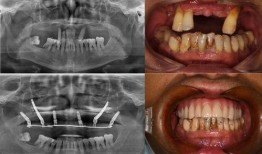

佛山种牙爆料事件最新,揭露行业乱象,患者权益如何保障?

最近佛山那边的种牙事件可是闹得沸沸扬扬的,咱们得好好来聊聊这个话题。你有没有想过,一颗牙齿的种植竟然能引发这么大的波澜?那就让我...